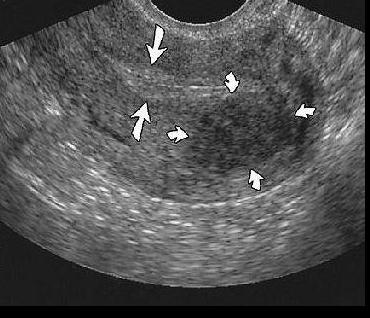

Эхографические ознаки раку ендометрію в постменопаузі включають в себе:

• заповнений рідиною канал;

• потовщену маткову порожнину;

• збільшену матку;

• ураження матки з зміною ехо-картини.

Навіть УЗД вже точно показує наявність і ступінь інвазії міометрія. Ці дослідження показали, що найбільш точна передопераційна діагностика може дозволити право вибору терапії, що, можливо, призведе до поліпшення результатів.

Якщо товщина ендометрію 8 мм або менше у пацієнтів з постклимактерическими кровотечами, то правильно поставити діагноз “рак ендометрія” можна шляхом вискоблювання. Тому при товщині ендометрію в постменопаузі 10 мм і більше слід проводити подальше обстеження з допомогою біопсії або вискоблювання, щоб виключити злоякісний характер або гіперплазію.Деякі дослідники продемонстрували корисність ультразвукової допплерографії в діагностиці раку ендометрію. Дослідники пояснили збільшення кровотоку в матковій артерії підозрою на пухлину у хворих зі злоякісними захворюваннями: ненормальний кровотік може бути виявлений практично у всіх випадках карциноми ендометрія, а також саркоми матки. З кольоровим доплером, аномальні знахідки включають наявність нерегулярних, тонких і хаотично розподілених судин і патологічної швидкості потоку сигналу.